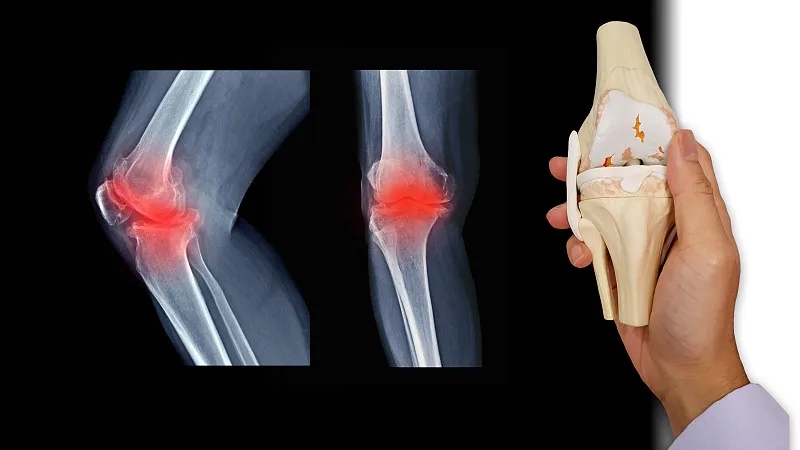

關(guān)節(jié)炎是一個通用術(shù)語,表示關(guān)節(jié)發(fā)炎。骨關(guān)節(jié)炎,俗稱磨損性關(guān)節(jié)炎,是最常見的關(guān)節(jié)炎類型。它與關(guān)節(jié)軟骨的破壞有關(guān),并且?guī)缀蹩梢园l(fā)生在身體的任何關(guān)節(jié)中。它通常發(fā)生在臀部、膝蓋和脊柱的負(fù)重關(guān)節(jié)中。它還會影響手指、拇指、頸部和大腳趾。

軟骨是一種堅硬的橡膠狀材料,覆蓋在正常關(guān)節(jié)的骨骼末端。它的主要功能是減少關(guān)節(jié)處的摩擦,起到“減震器”的作用。正常軟骨的減震特性來自其在受壓(壓平或壓在一起)時改變形狀的能力。

骨關(guān)節(jié)炎導(dǎo)致關(guān)節(jié)中的軟骨變硬并失去彈性,使其更容易受到損傷。隨著時間的推移,軟骨可能會在某些區(qū)域磨損,從而大大降低其作為減震器的能力。隨著軟骨退化,肌腱和韌帶伸展,引起疼痛。如果情況惡化,骨頭可能會相互摩擦。

如何診斷骨關(guān)節(jié)炎?

您的醫(yī)生可能會使用X光檢查來幫助確認(rèn)診斷并確保您沒有其他類型的關(guān)節(jié)炎。X 射線顯示發(fā)生了多少關(guān)節(jié)損傷。如果X射線結(jié)果不能明確指出關(guān)節(jié)炎或其他疾病,則可能需要進(jìn)行MRI以更好地觀察關(guān)節(jié)和周圍組織。